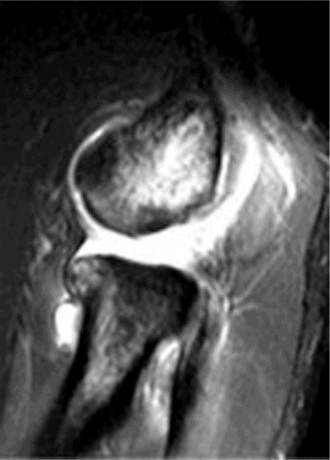

any activity in which the arm is extended and externally rotated while under maximal contraction (eccentric loading force). Patients often present with pain, swelling, ecchymosis, weakness and loss of the axillary fold in the acute setting. In the chronic setting, the swelling and ecchymosis have typically subsided. They may report an audible pop or a tearing sensation. On examination, there can be an apparent continuous muscle or tendon that is mistaken for an intact PMM tendon, but this represents the fascia of the PMM that is continuous with the fascia of both the brachium and the medial antebrachial septum. This continuous fascia will examine as a cord-like structure as shown in Figure 2–78.

Figure 2–78

After evaluating the MRI, the patient is diagnosed with a complete rupture of the pectoralis major tendon (Fig. 2–79). What is the recommended first step in management?

Figure 2–79